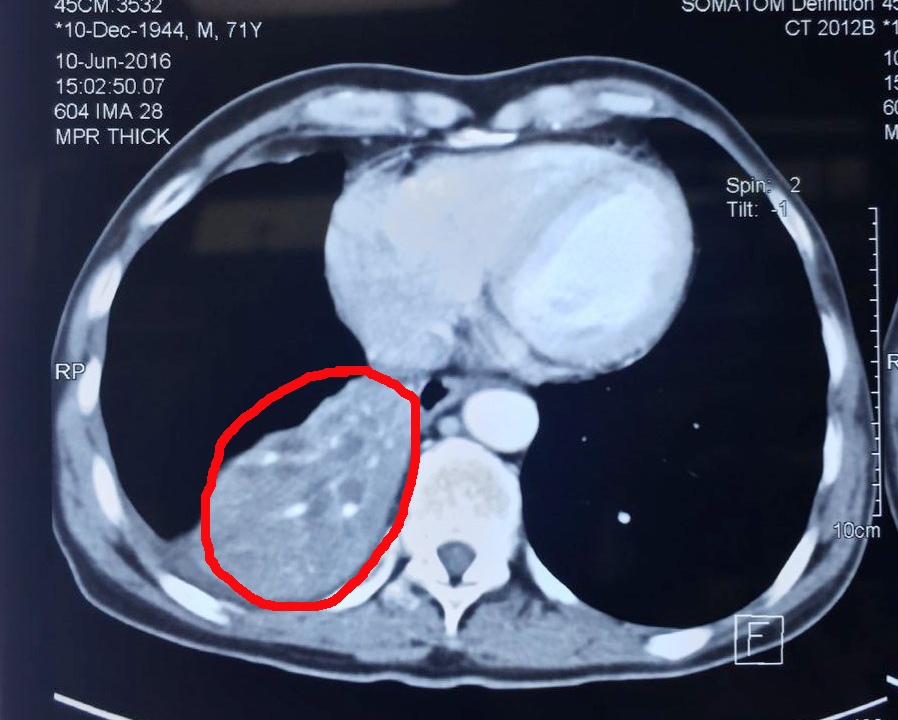

腫瘤治療前